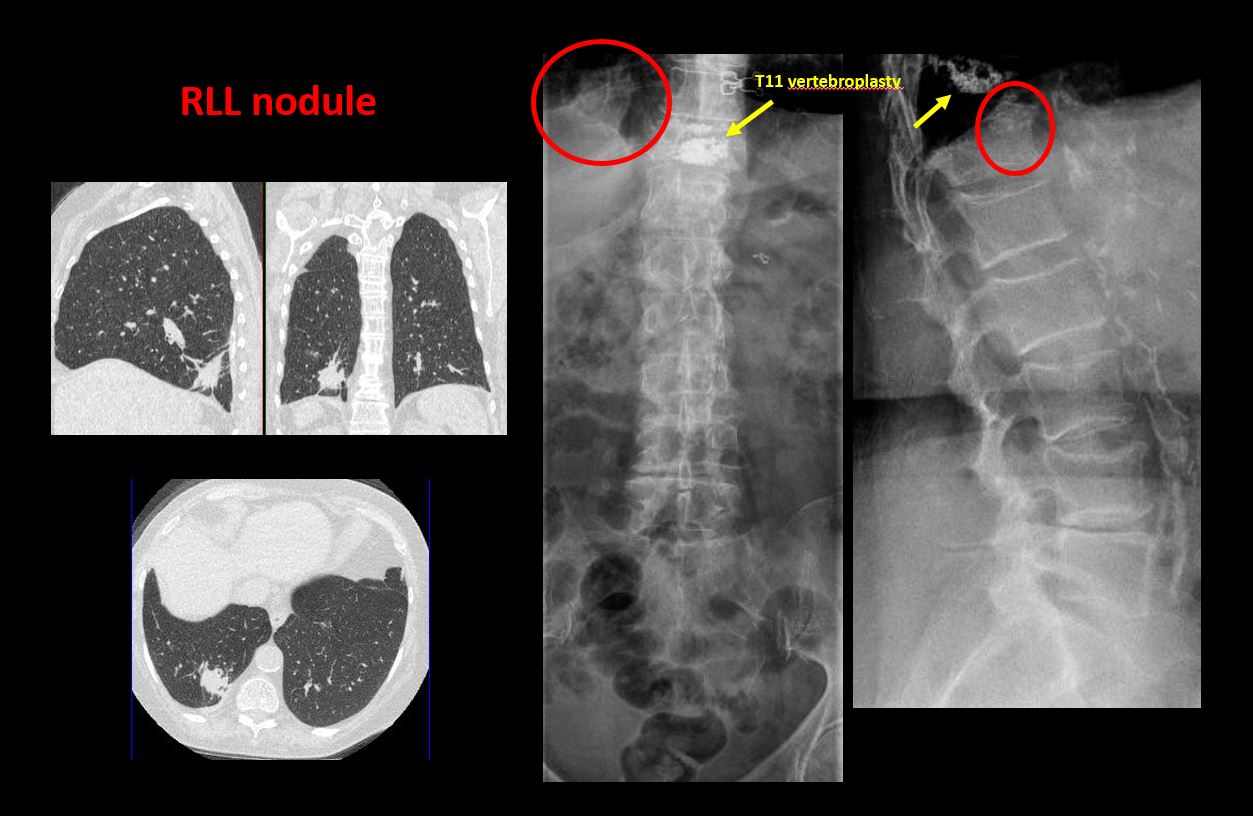

There is a fracture or distraction of a vertebral body, transverse or spinous process, or other posterior element. |

There is anterior wedging and/or compression of a vertebral body or end plate. |

There is a fracture, erosion, sclerosis, lytic, or blastic lesion of a pedicle or lamina. |

There is evidence of a lytic or sclerotic lesion, or disruption of the trabecular pattern of a vertebral body, end plate, or sacrum. |

3There is a lytic lesion of the L4 vertebral body. There is compression of the L4 vertebral body which is likely pathologic. Possible etiologies include metastatic disease or primary neoplasm such as myeloma.

Direct communication with the referring physician at the time of dictation regarding the lytic lesion of L4 and the findings of a likely pathologic fracture. Further imaging is recommended.